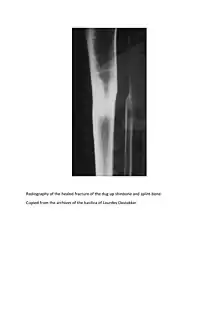

De Rudder was working for the Viscount Albéric du Bus de Gisignies when on February 16, 1867, in Jabbeke (West Flanders), a falling tree broke the two bones (tibia and fibula) of his left leg.[3]